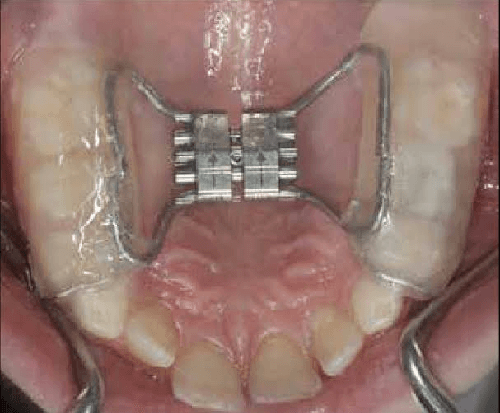

Rapid Maxillary Expansion

Orthodontic procedure used to widen the upper jaw in children and adolescents. This treatment corrects crossbites and creates space for crowded teeth by expanding the palatal suture.